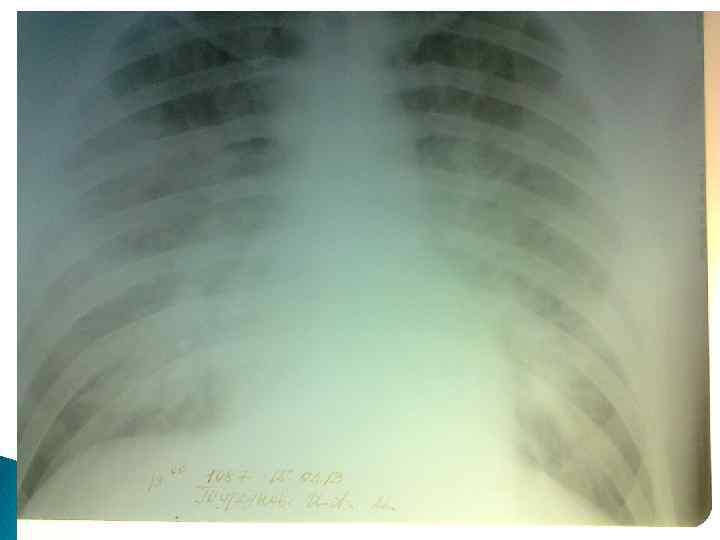

КЛИНИЧЕСКИЙ СЛУЧАЙ: ИБ№ 2984 Больной Ш. Дата рождения: 22. 05. 1990 г. Дата поступления: 27. 12. 2012 Дата выписки: 14. 01. 2013 Диагноз : Внебольничная верхнедолевая правосторонняя пневмония.

Анамнез Morbi: ü со слов больного и данных медицинских документов болен в течение 3 -х дней, когда после переохлаждения появились сухой кашель, заложенность носа и общая слабость, к врачу не обращался ü Ухудшение состояния 26. 12 почувствовал жар во всем теле, температура 41, 0 С, боли в грудной клетке при дыхательных движениях, кашель с мокротой и общую слабость. ü Обратился в МП части, назначена инфузионная терапия. 27. 12 проведена РГОГК: Правосторонняя среднедолевая пневмония. Направлен в ВКГ МО РК. Госпитализирован в терапевтичекое отделение.

В стационаре : РГОГК от 04. 01. 13 г. Верхнедолевая правосторонняя пневмония. Температура с 28. 12 - 37, 2 С и до 03. 01. 13 г 36, 2 С ОАК от 28. 12 Нв-134, эрит-4, 4, лейк-5, 3, СОЭ-21. ОАМ: лейк-3 -4 в пзр, бактерии (+), оксалаты(++) БАК : алт-70, аст-48, белок-70, мочевина 6, 7, креатитин-83, ХС-2 ЭКГ: ритм синусовый, ЧСС-83, ЭОСвправо, перегрузка правого предсердия, дифузные изменения миокарда Микроскопия мокроты: степт. , чувствит. к ципрофлоксацину, цефтриаксону, цефалексину